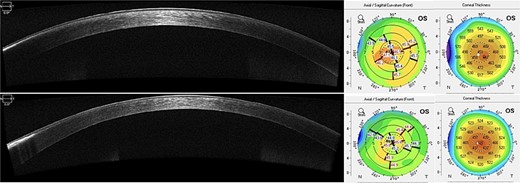

Scheimpflug imaging (Pentacam HR, Oculus Wetzlar, Germany) revealed irregular astigmatism, as shown by sagittal curvature maps and anterior elevation maps, with a central corneal thickness of 461 μm (Fig. 3).

Scheimpflug imaging showing irregular astigmatism and superficial irregularity.

AS-OCT revealed an improvement in the hyper reflective band in the treated area. Scheimpflug imaging displayed superficial regularization and a predictable decrease in central corneal thickness of 20 μm (Fig. 4).

AS-OCT at 1-year postoperatively shows improvement of the paracentral hyper reflective band. A worsening in the peripheral untreated are can also be noticed. Scheimpflug imaging demonstrates thinning of central corneal thickness and reduction of mean anterior keratometry (45.3D) with superficial regularization.